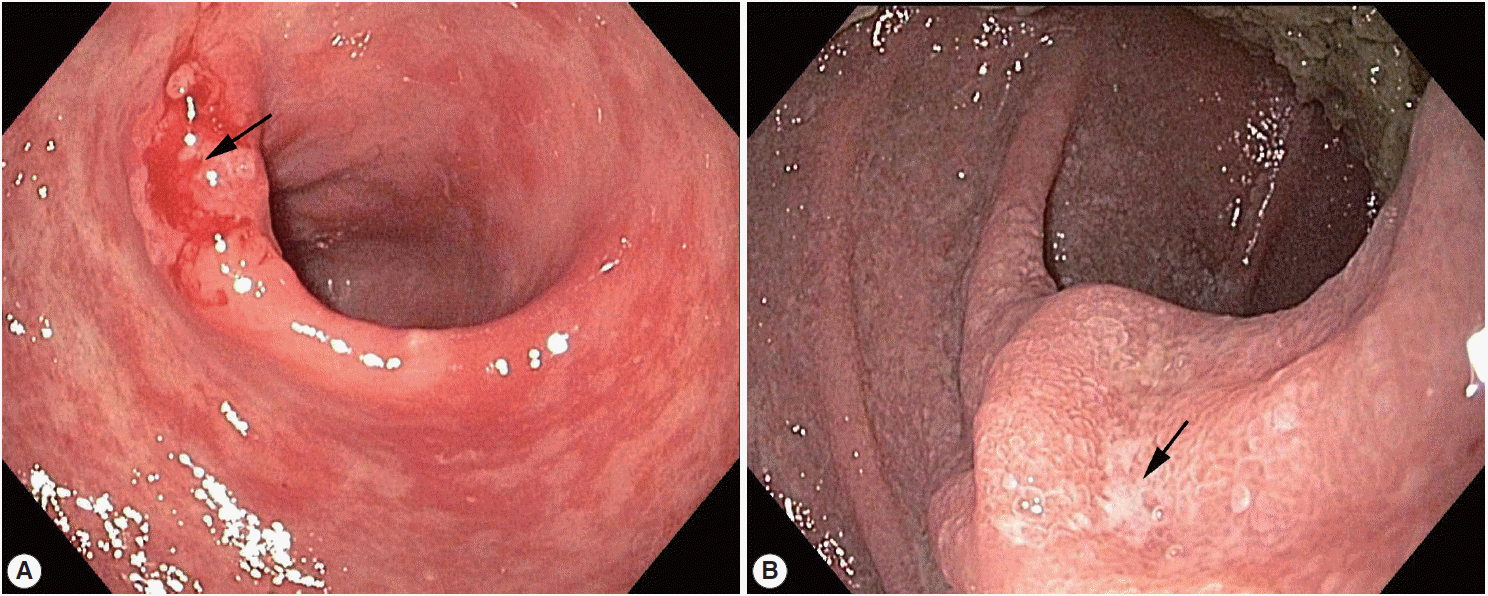

An 81-year-old Korean man presented with weight loss, poor oral intake, and abdominal discomfort for 3 months in November 2013. Although the patient had hypertension and diabetes mellitus for several years and had been treated with standard medication, he was relatively healthy until recently. Physical examination showed no signs of fever, chills, diarrhea, abnormal bowel movement or sound, or skin rash. Furthermore, the patient did not report any previous intake of alcohol, tobacco, herb mediation, or inhaled corticosteroids. In addition, he had no significant family history or recent history of travel to tropical or subtropical regions. Esophagogastroduodenoscopy revealed chronic atrophic gastritis with intestinal metaplasia and multiple erosions in the stomach; in particular, an ulcerative lesion, suggestive of type IIc early gastric cancer, was observed in the anterior wall of the antrum, and an atrophic lesion was observed in the duodenum (Fig. 1). Microscopic examination of a biopsy specimen from the gastric mass in the antrum revealed a well-differentiated adenocarcinoma as well as parasite eggs, rhabditiform larvae, and adult worms presumably of S. stercoralis in normal gastric pits. Scattered eosinophils were not generally observed in the antrum (Fig. 2A); however, some parasite eggs and adult worms were observed along with scattered eosinophils in the mucosa of normal duodenal pits (Fig. 2B).